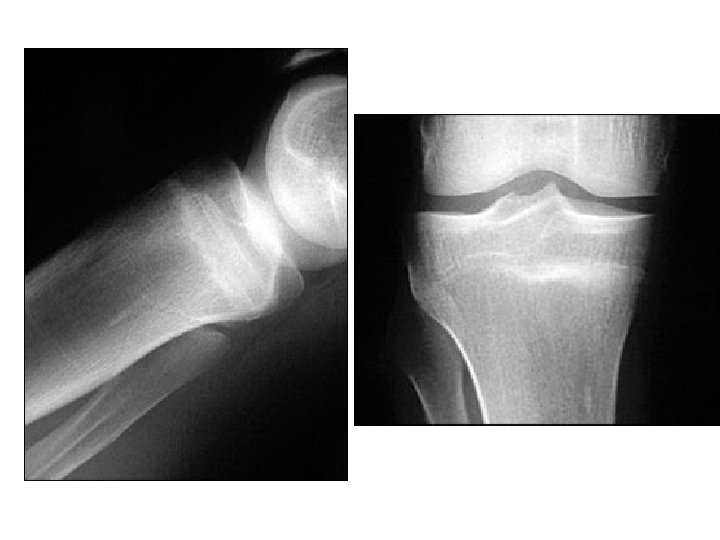

Persistent Anterior Knee Pain n A 20 year old military recruit presented for follow up of anterior knee pain. Previously, he presented with three weeks of right knee pain without trauma, swelling, locking, or instability. At that visit, he was referred for physical therapy, but the knee did not improve during treatment. On recent examination, the patient had a positive “theater sign” (i. e. , knee pain upon arising after prolonged sitting), positive patellar compression and inhibition tests, stable ligaments, pain with Mc. Murray's test, and tenderness of the medial tibial plateau.

Atraumatic, Persistent, Anterior Knee Pain

Discussion n The answer is E: proximal tibial stress fracture. Most tibial stress fractures occur in the tibial diaphysis. However, proximal tibial stress fractures, typically involving the medial condyle, can occur in athletes. Stress fractures may result from weaker bone that fails under normal loading (i. e. , an insufficiency fracture) or normal bone that fails under new or increased repetitive loading (i. e. , a fatigue fracture). Athletes are more likely to experience a fatigue fracture; military recruits are also at risk. Drabicki RR, Greer WJ, De. Meo PJ. Stress fractures around the knee. Clin Sports Med. 2006; 25: 105– 15. Raasch WG, Hergan DJ. Treatment of stress fractures: the fundamentals. Clin Sports Med. 2006; 25: 29– 36.

Discussion n Medical history that suggests a stress fracture will include persistent pain following an acute increase in physical activity (i. e. , time, distance, or pace). Physical examination may reveal tenderness at or near the medial joint line, tenderness with a leverage motion, and tenderness with hopping on the affected leg. A joint effusion may also be present.

Discussion n Plain radiographs can appear normal for weeks or even months. Because the metaphyseal portions of long bones are mostly cancellous bone, the typical periosteal/endosteal reaction will not be visible. In this type of bone, the features of a stress fracture manifest as a band-like area of sclerosis. If a stress fracture is suspected but radiographic results are normal, then magnetic resonance imaging (MRI) or a bone scan is the next diagnostic study. Of the two, MRI is more sensitive for diagnosing stress fracture.